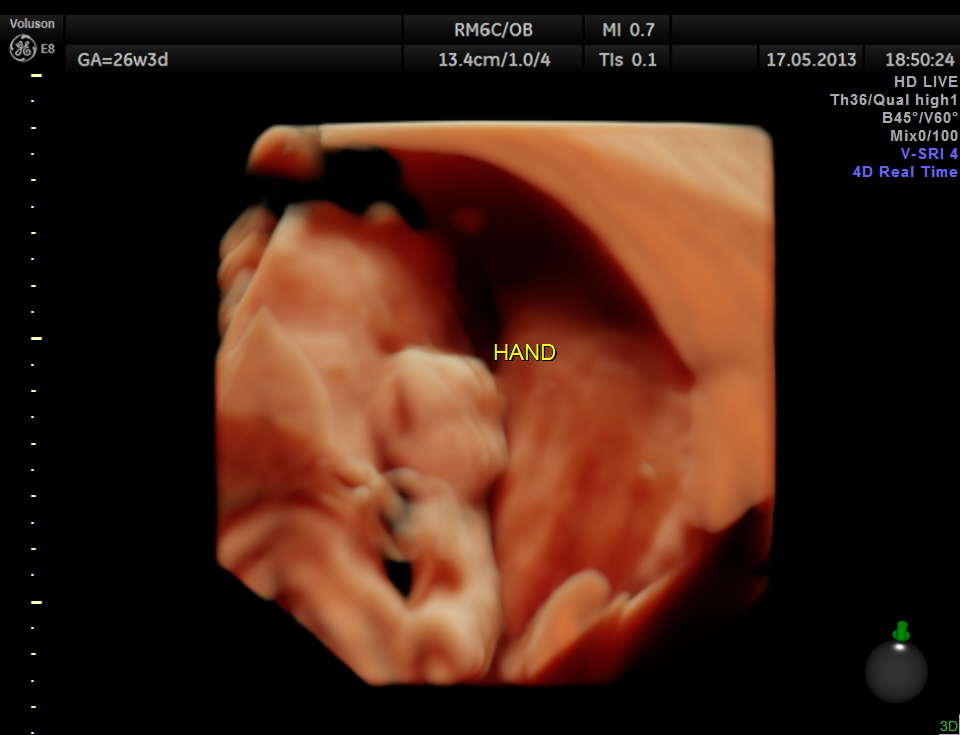

The limbs are shown below.